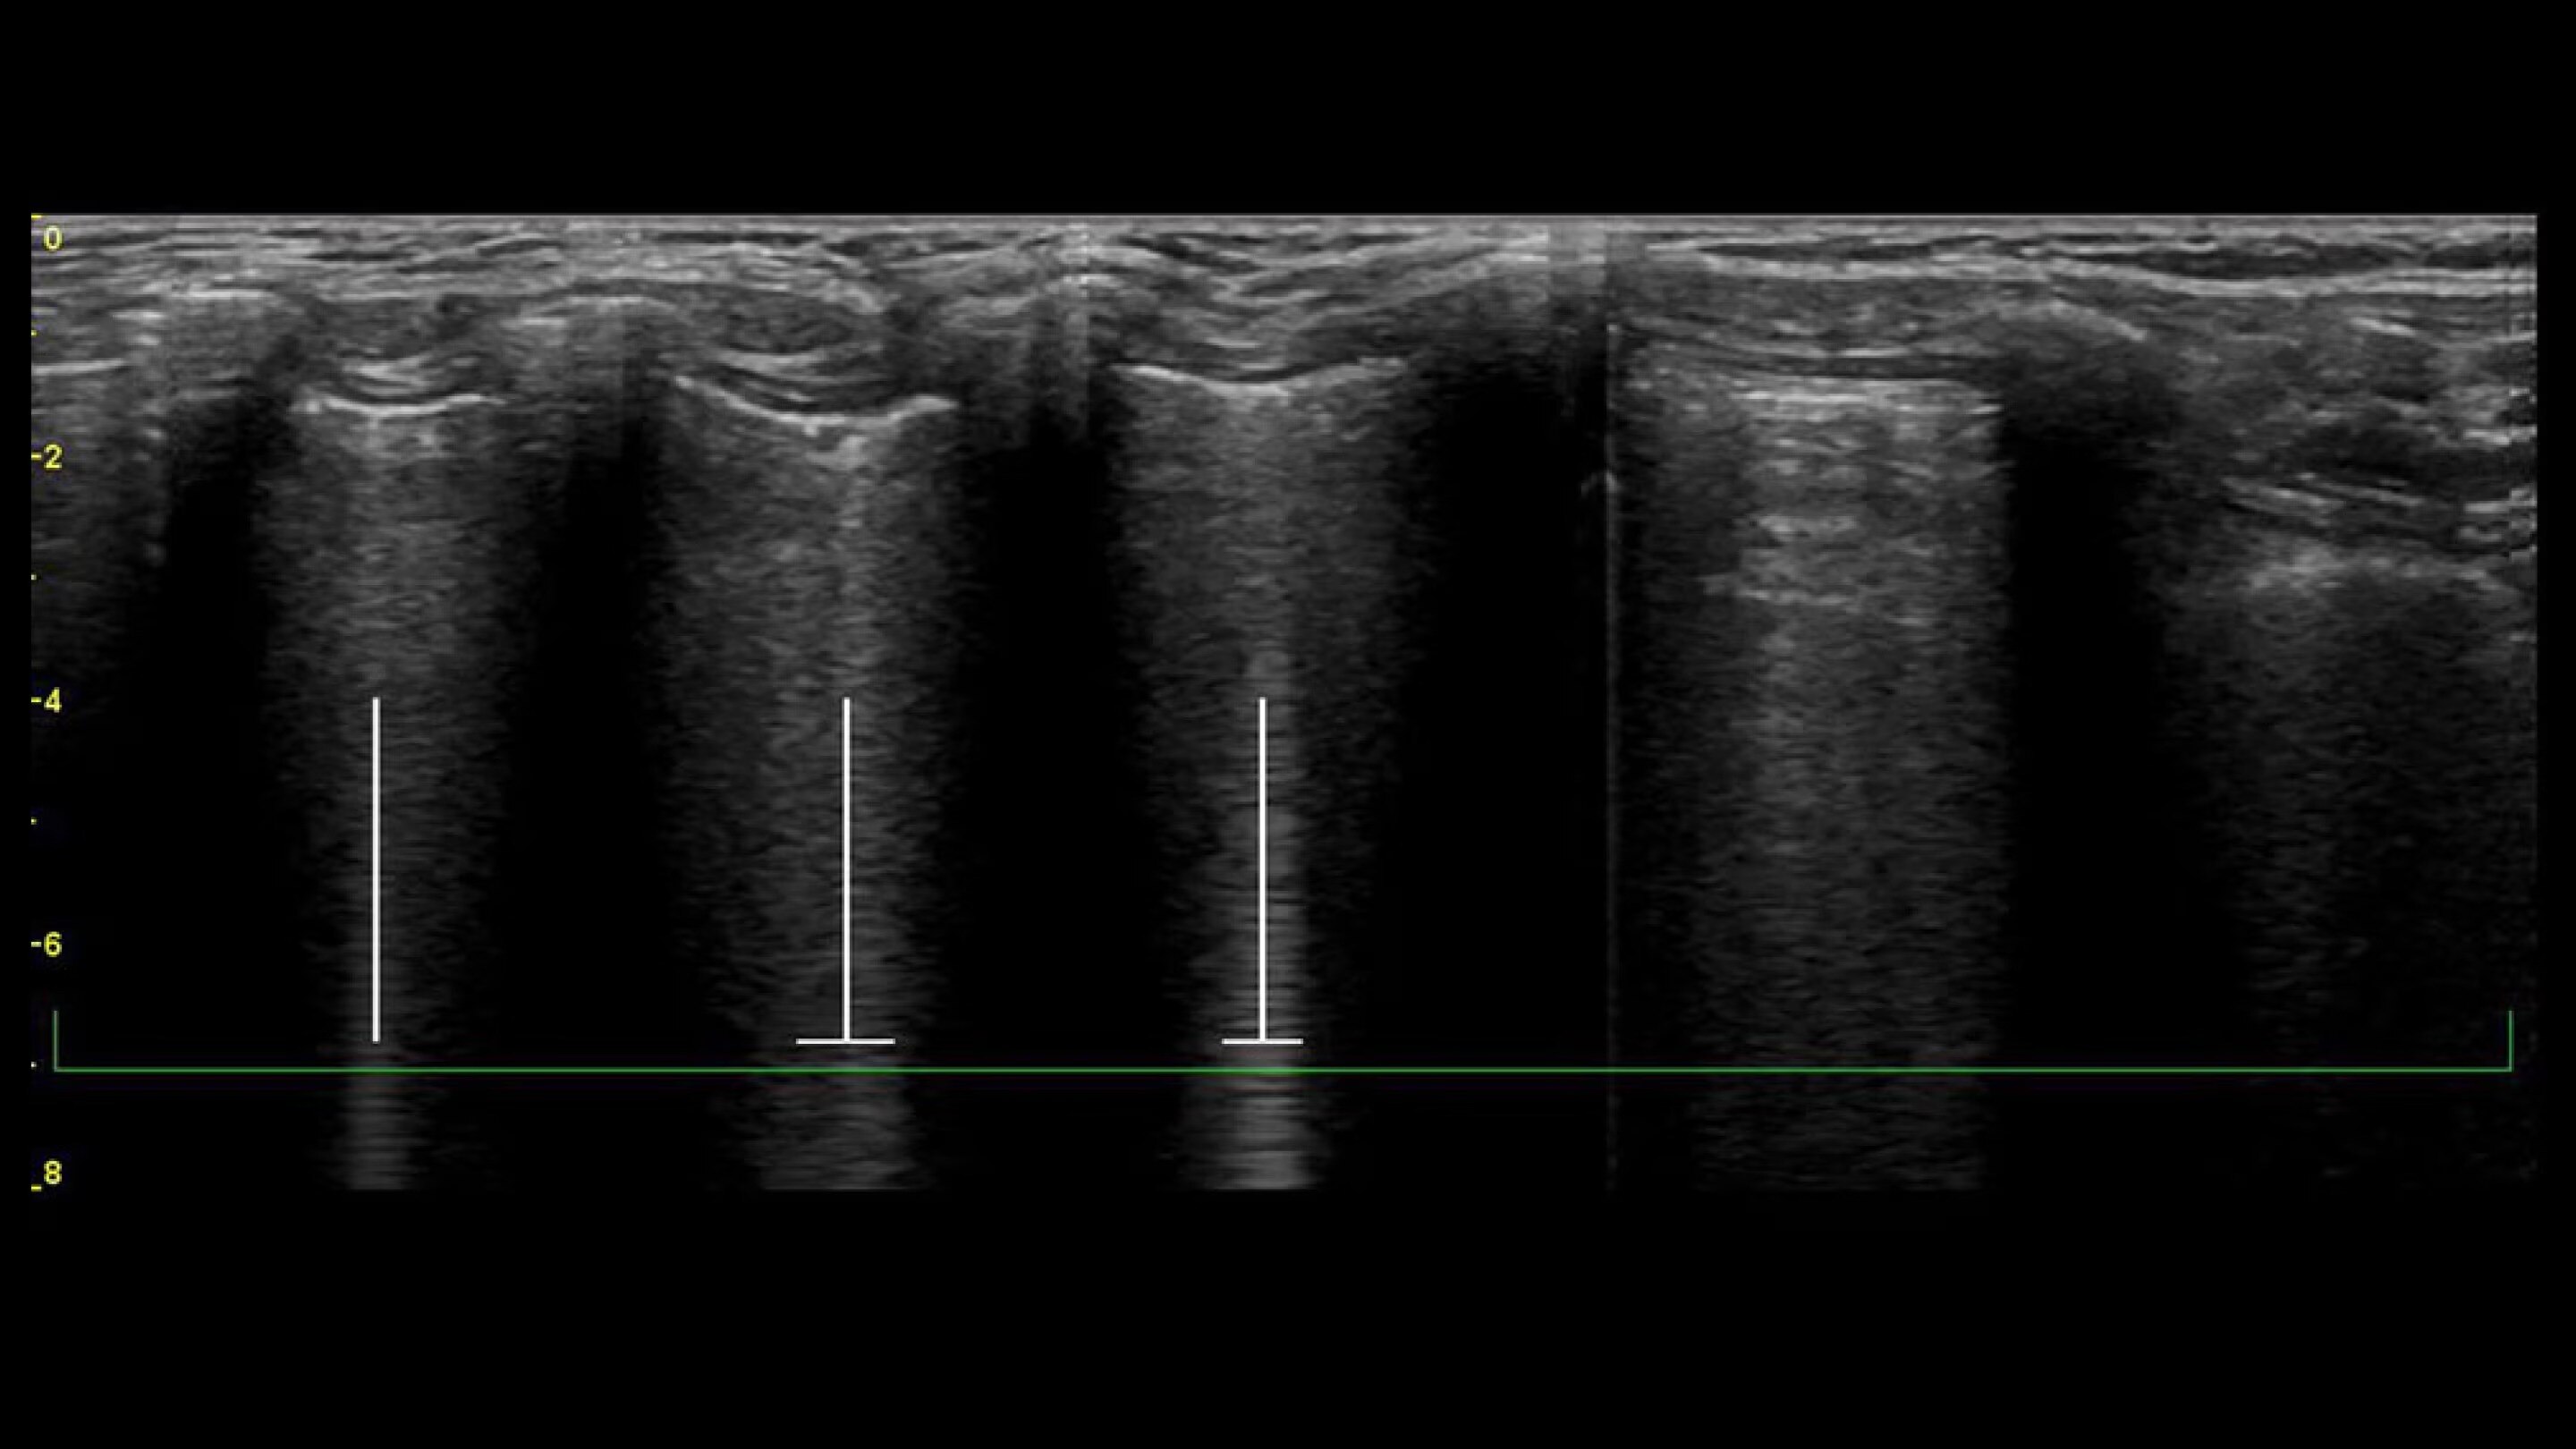

Auto B-Lines

Highlight and count B-lines, in real time

With the Auto B-Lines tool, you can calculate overall lung score in one step. Use it in conjunction with Lung Sweep to highlight B-lines and display the frame with the most B-lines per rib space.